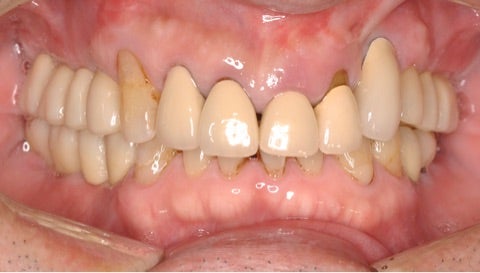

初診時

▶︎実際両側の奥歯には計10本以上のインプラントが埋入されています。

after

▶︎手術の傷口もほとんどわからない程度まで回復しています。(写真右上前歯部分)

before/after

歯の動揺がなくなったことはもちろん、歯と歯茎の黒い境目や、形態不良による審美障害も改善されています。ご本人には自分の歯が残せたこと、見た目も綺麗になったことでとても喜んで頂けました。